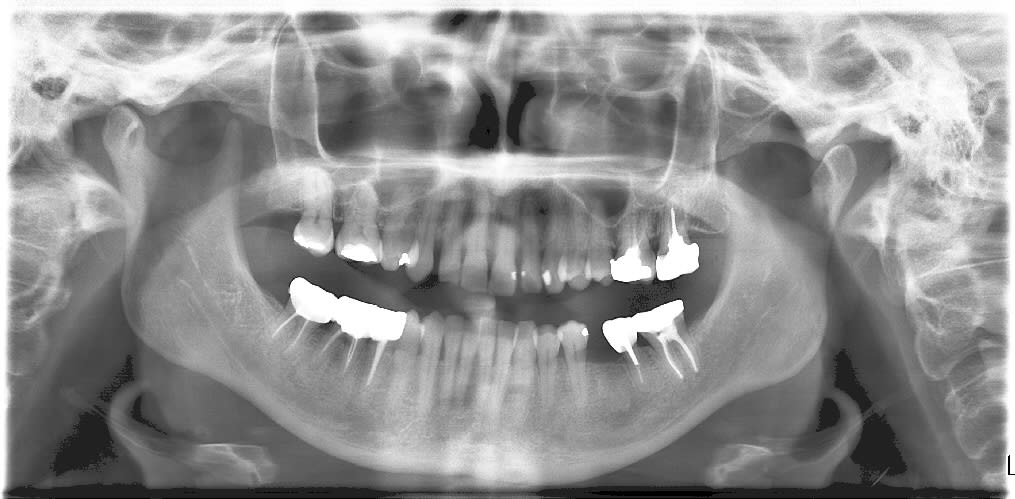

20 ans. La flemme d'aller chercher la radio analogique de 97 et de la scanner avec le scanner a dos retro éclairé....Conditions idéales, je sais....

Image2 x8gkpk - Eugenol

tu feras gaffe adhoc on arrive a lire l'identité de la patiente sur ton opt.

Merci chef, je la reprends sur Paint shop pro!!! Mais je vois rien!!!! (je cherche!!!)

EDIT: j'ai gommé un peu plus, est ce qu'on le voit encore?

Recadrage, c'est nickel. C'est pas possible de voir des infos qui n'existent pas.